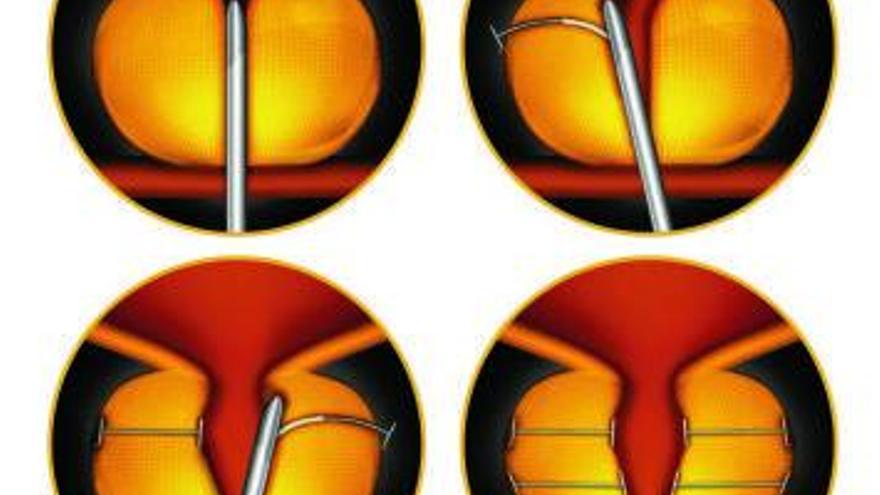

Cirugía con el sistema Urolift. / Pablo Llana

Se trata de un procedimiento endoscópico, a través de la uretra, con anestesia local más sedación, en régimen ambulatorio (alta hospitalaria a las 2 o 3 horas de la cirugía) siendo una de sus principales ventajas la inmediatez de los resultados tras la cirugía.

La intervención quirúrgica es mínimamente invasiva, y consiste en colocar implantes que hacen la función de cinchas o cinturones que comprimen el crecimiento prostático logrando ampliar la luz por donde sale la orina.